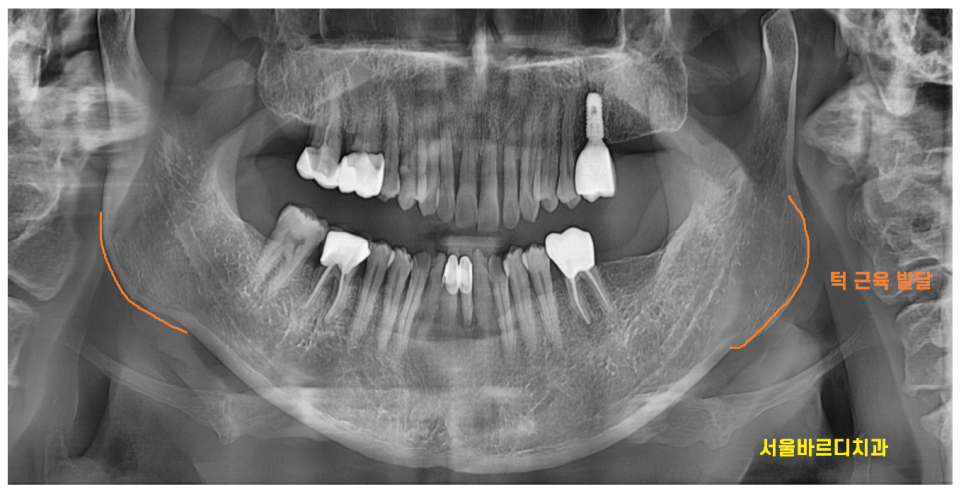

환자분이 턱 뼈가 발달된 것을 보니

씹는 힘이 좋으신 환자분입니다~

위 아래 어금니 2개 없다고

씹는게 크게 달라지겠어? 생각하실 수도 있겠지만

간혹 그 미세한 힘의 균형 차이를 느끼는 분들이 있답니다